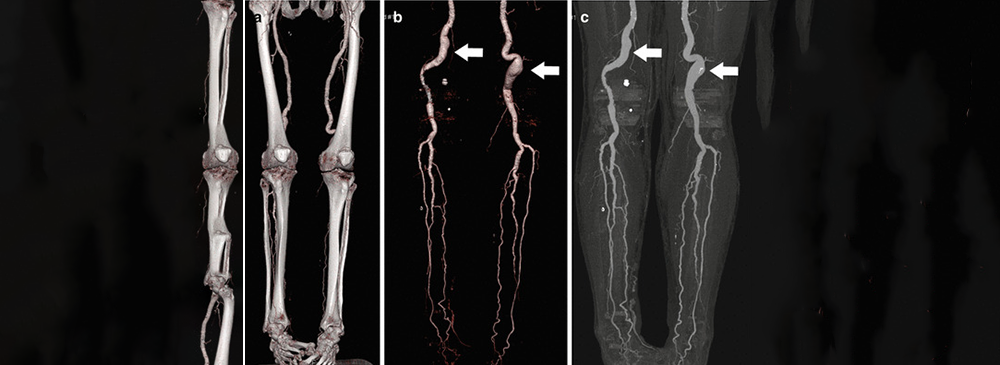

The CT Lower Limb Angiogram focuses on evaluating the arteries in the legs, an area commonly affected by circulation problems such as peripheral artery disease (PAD). Patients with pain while walking, cold feet, or wounds that don’t heal may be advised to undergo this test. Left untreated, poor circulation in the legs can lead to serious complications, including ulcers and, in severe cases, tissue loss.

Our centre uses high‑resolution CT technology that captures even the smallest abnormalities in the blood vessels. This allows doctors to determine the severity of the condition and plan treatments ranging from medication to surgical interventions. With our compassionate care team, you can undergo this important test with confidence, knowing you’ll receive both accuracy and support.

• Key test for diagnosing peripheral artery disease (PAD)

• Identifies blockages, narrowing, or poor circulation in legs